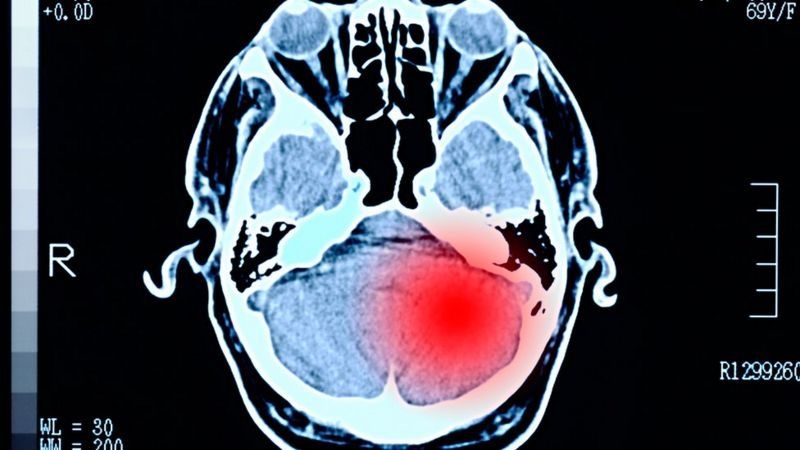

- Tumores cerebrales

De acuerdo al profesor Stark, los tumores que representan un mayor reto para adolescentes y adultos jóvenes son los tumores cerebrales y los carcinomas, especialmente los alojados en el tracto digestivo.

"Los tumores cerebrales son un reto porque las posibilidades de tratamiento y los pronósticos de recuperación son extremadamente pobres", dice el especialista.

Según el experto Daniel Stark, los tumores cerebrales apenas han cambiado su epidemiología en los últimos años.

Según el Servicio Nacional de Salud británico (NHS), los tumores cerebrales pueden manifestarse con dolores de cabeza, convulsiones, mareos, náuseas recurrentes, problemas de memoria, cambios de personalidad, debilidad y parálisis progresivas en una parte del cuerpo y problemas de visión o habla.